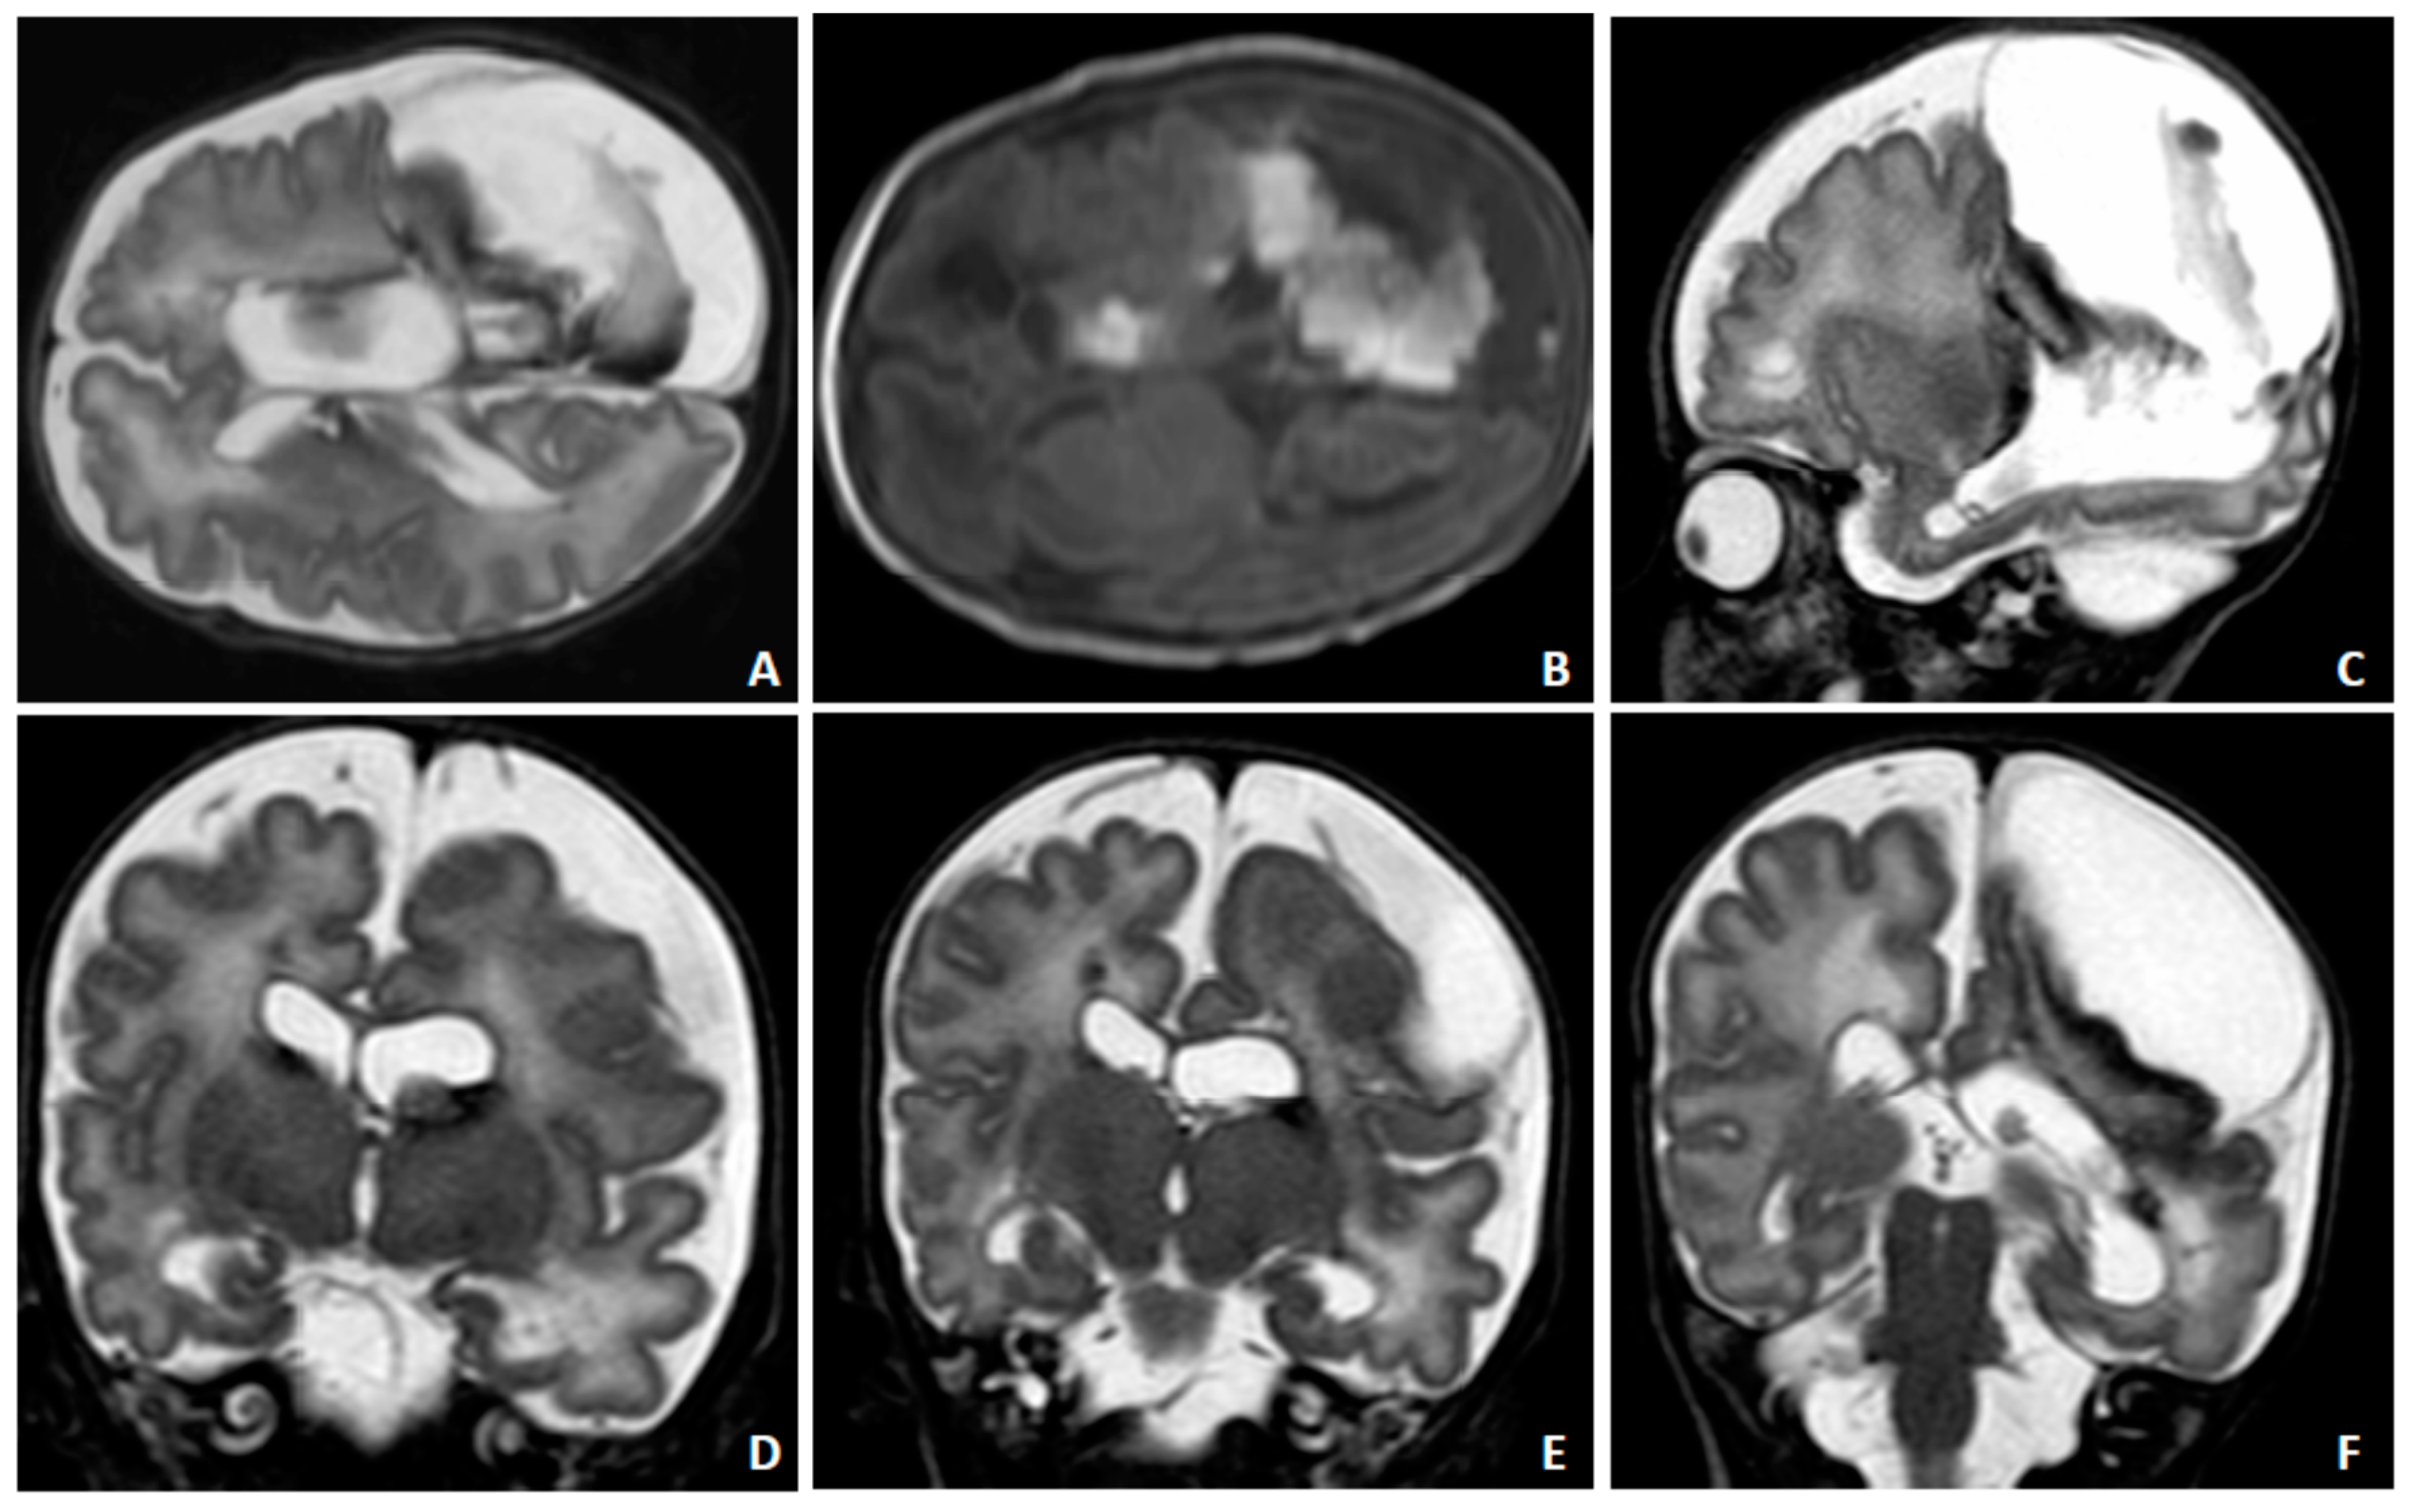

2. Case Presentation